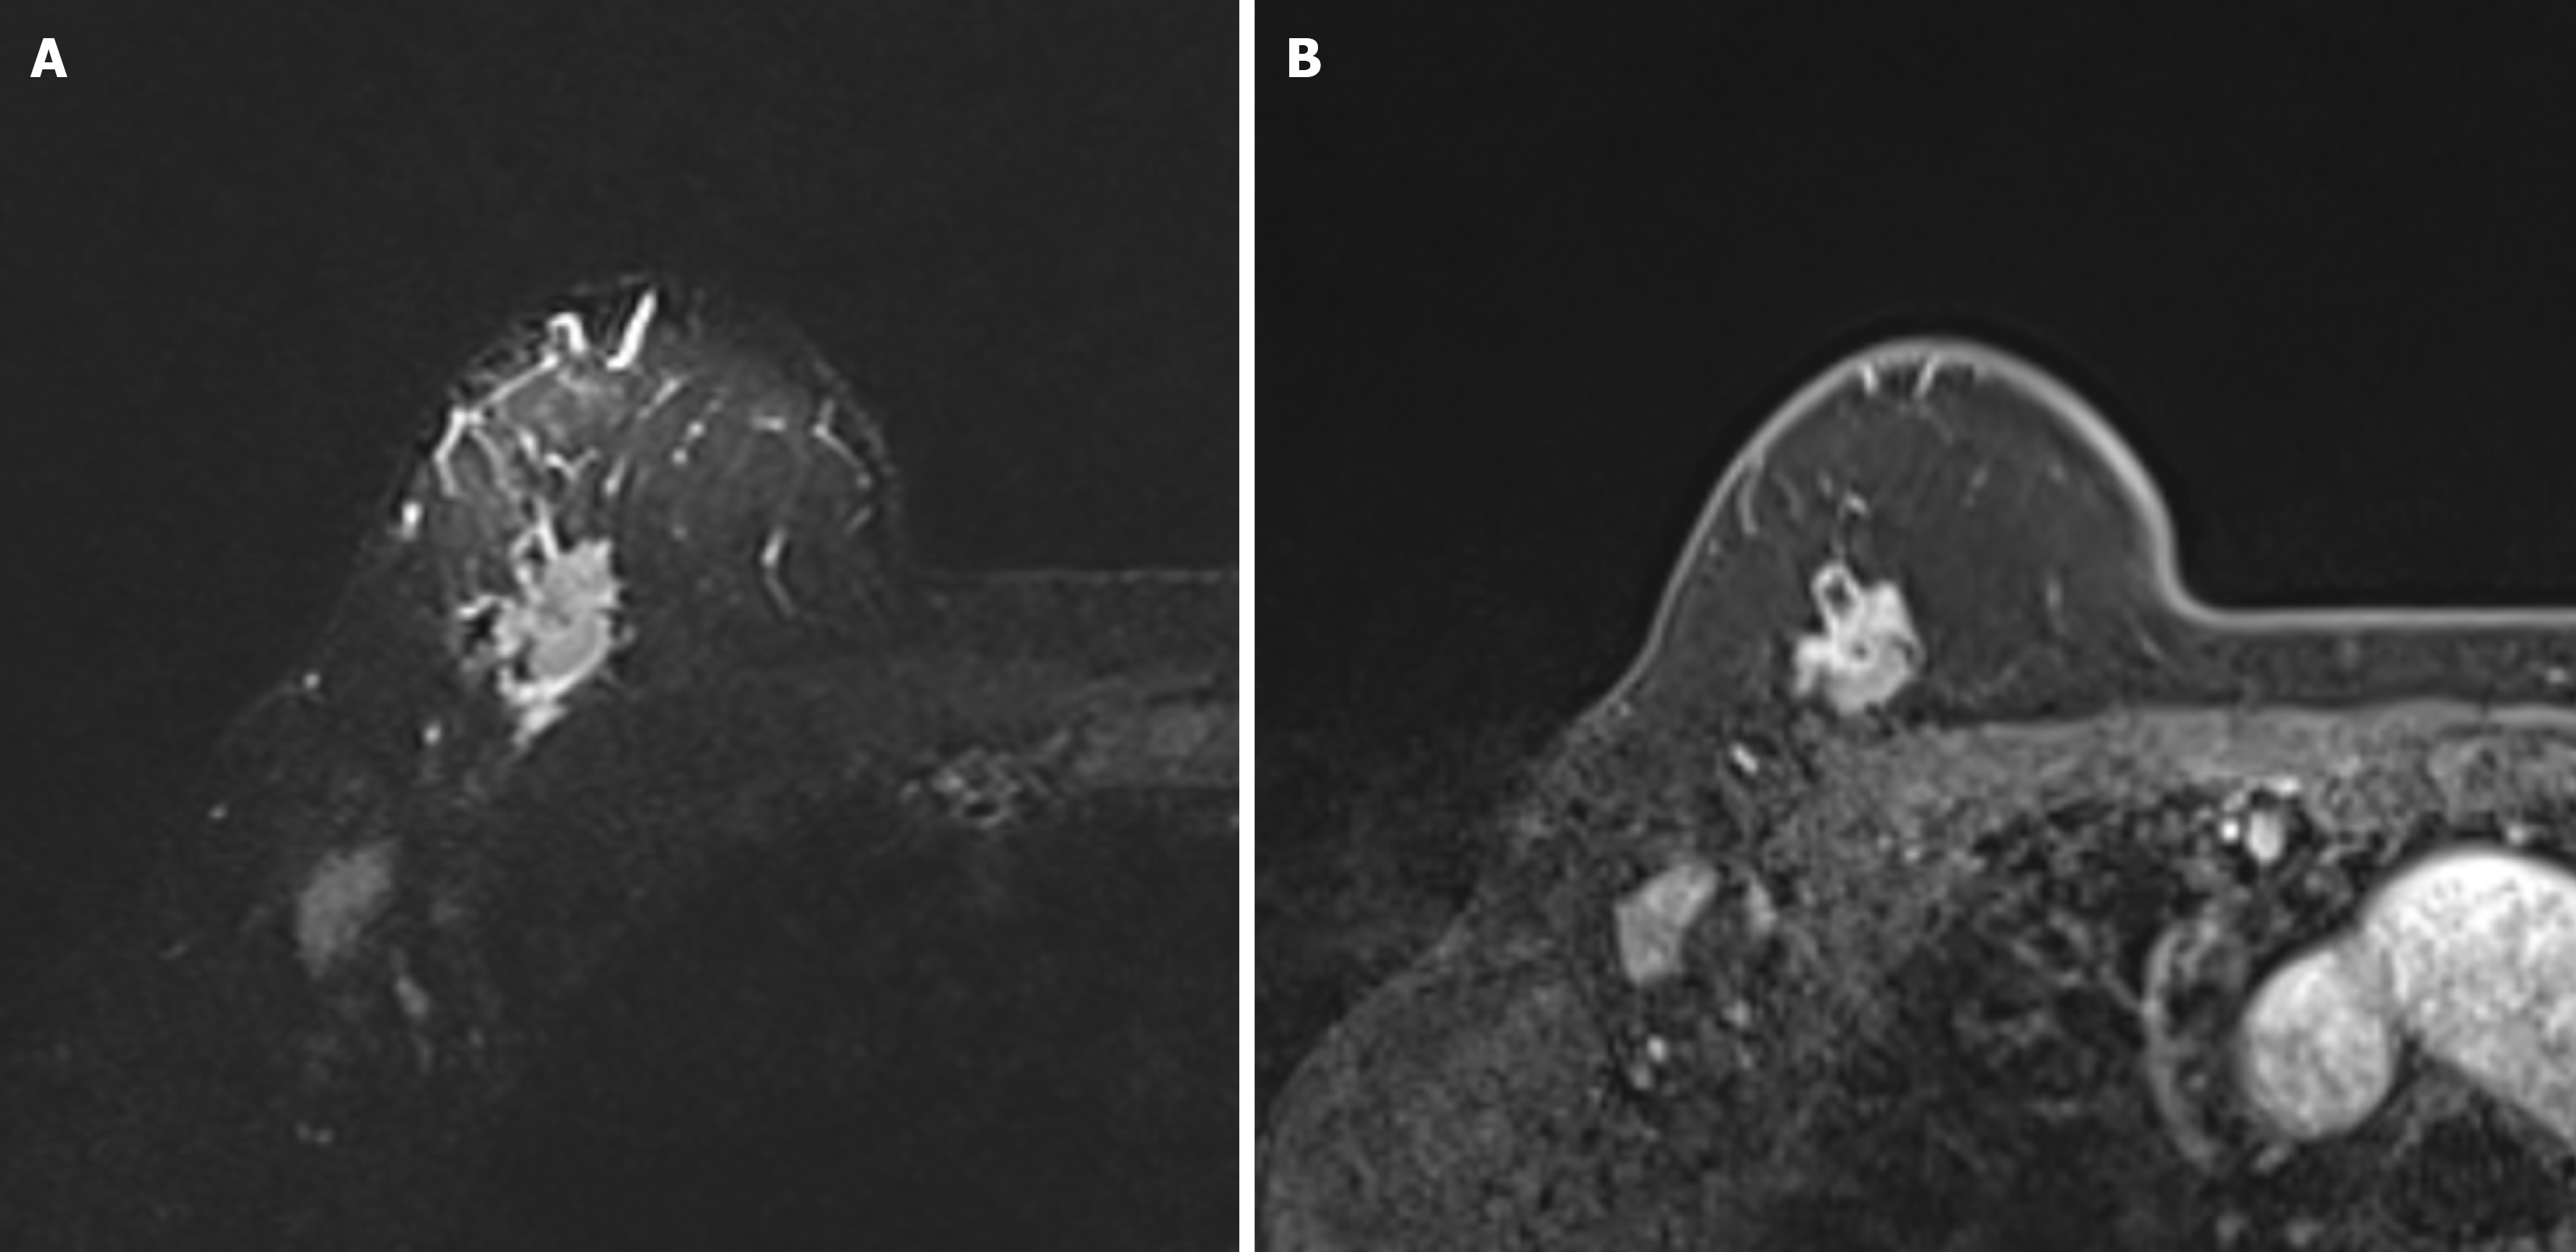

Figure 3 A 57-year-old woman with right breast invasive ductal carcinoma-no special type, triple-negative breast cancer.

A: Axial turbo inversion recovery magnitude image shows prepectoral edema without contrast enhancement on; B: Axial dynamic fat-suppressed contrast-enhanced 3D T1-WI.